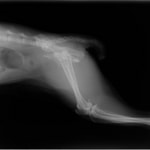

術前レントゲン